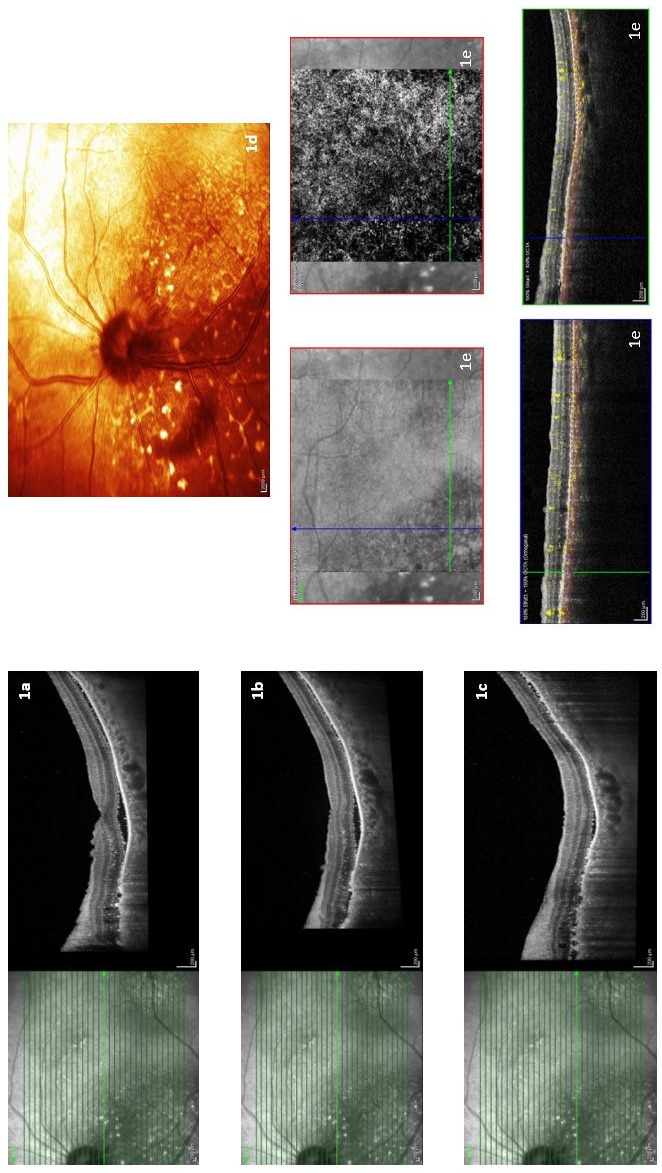

Case report: A 74-year-old male patient had undergone operation due to the diagnosis of rectum cancer two years ago, and lung (L) metastasis developed in the 4th month after the adjuvant therapy, but he refused to receive treatment and remained out of follow-up. The patient presented with complaints of decreased vision and light flashes in his eye 21 months after the diagnosis.

Management and outcome: Ocular examination revealed a choroidal mass and radiologically choroidal and multiple brain metastases were detected. In our case, whole-brain radiotherapy was administered in the treatment since there were also multiple brain metastases. However, as the ECOG (Eastern Cooperative Oncology Group) performance status of the patient was 3-4 after radiotherapy, systemic treatment was not considered appropriate, and the best supportive care was given. The patient died 2 months after the diagnosis of choroidal metastasis.